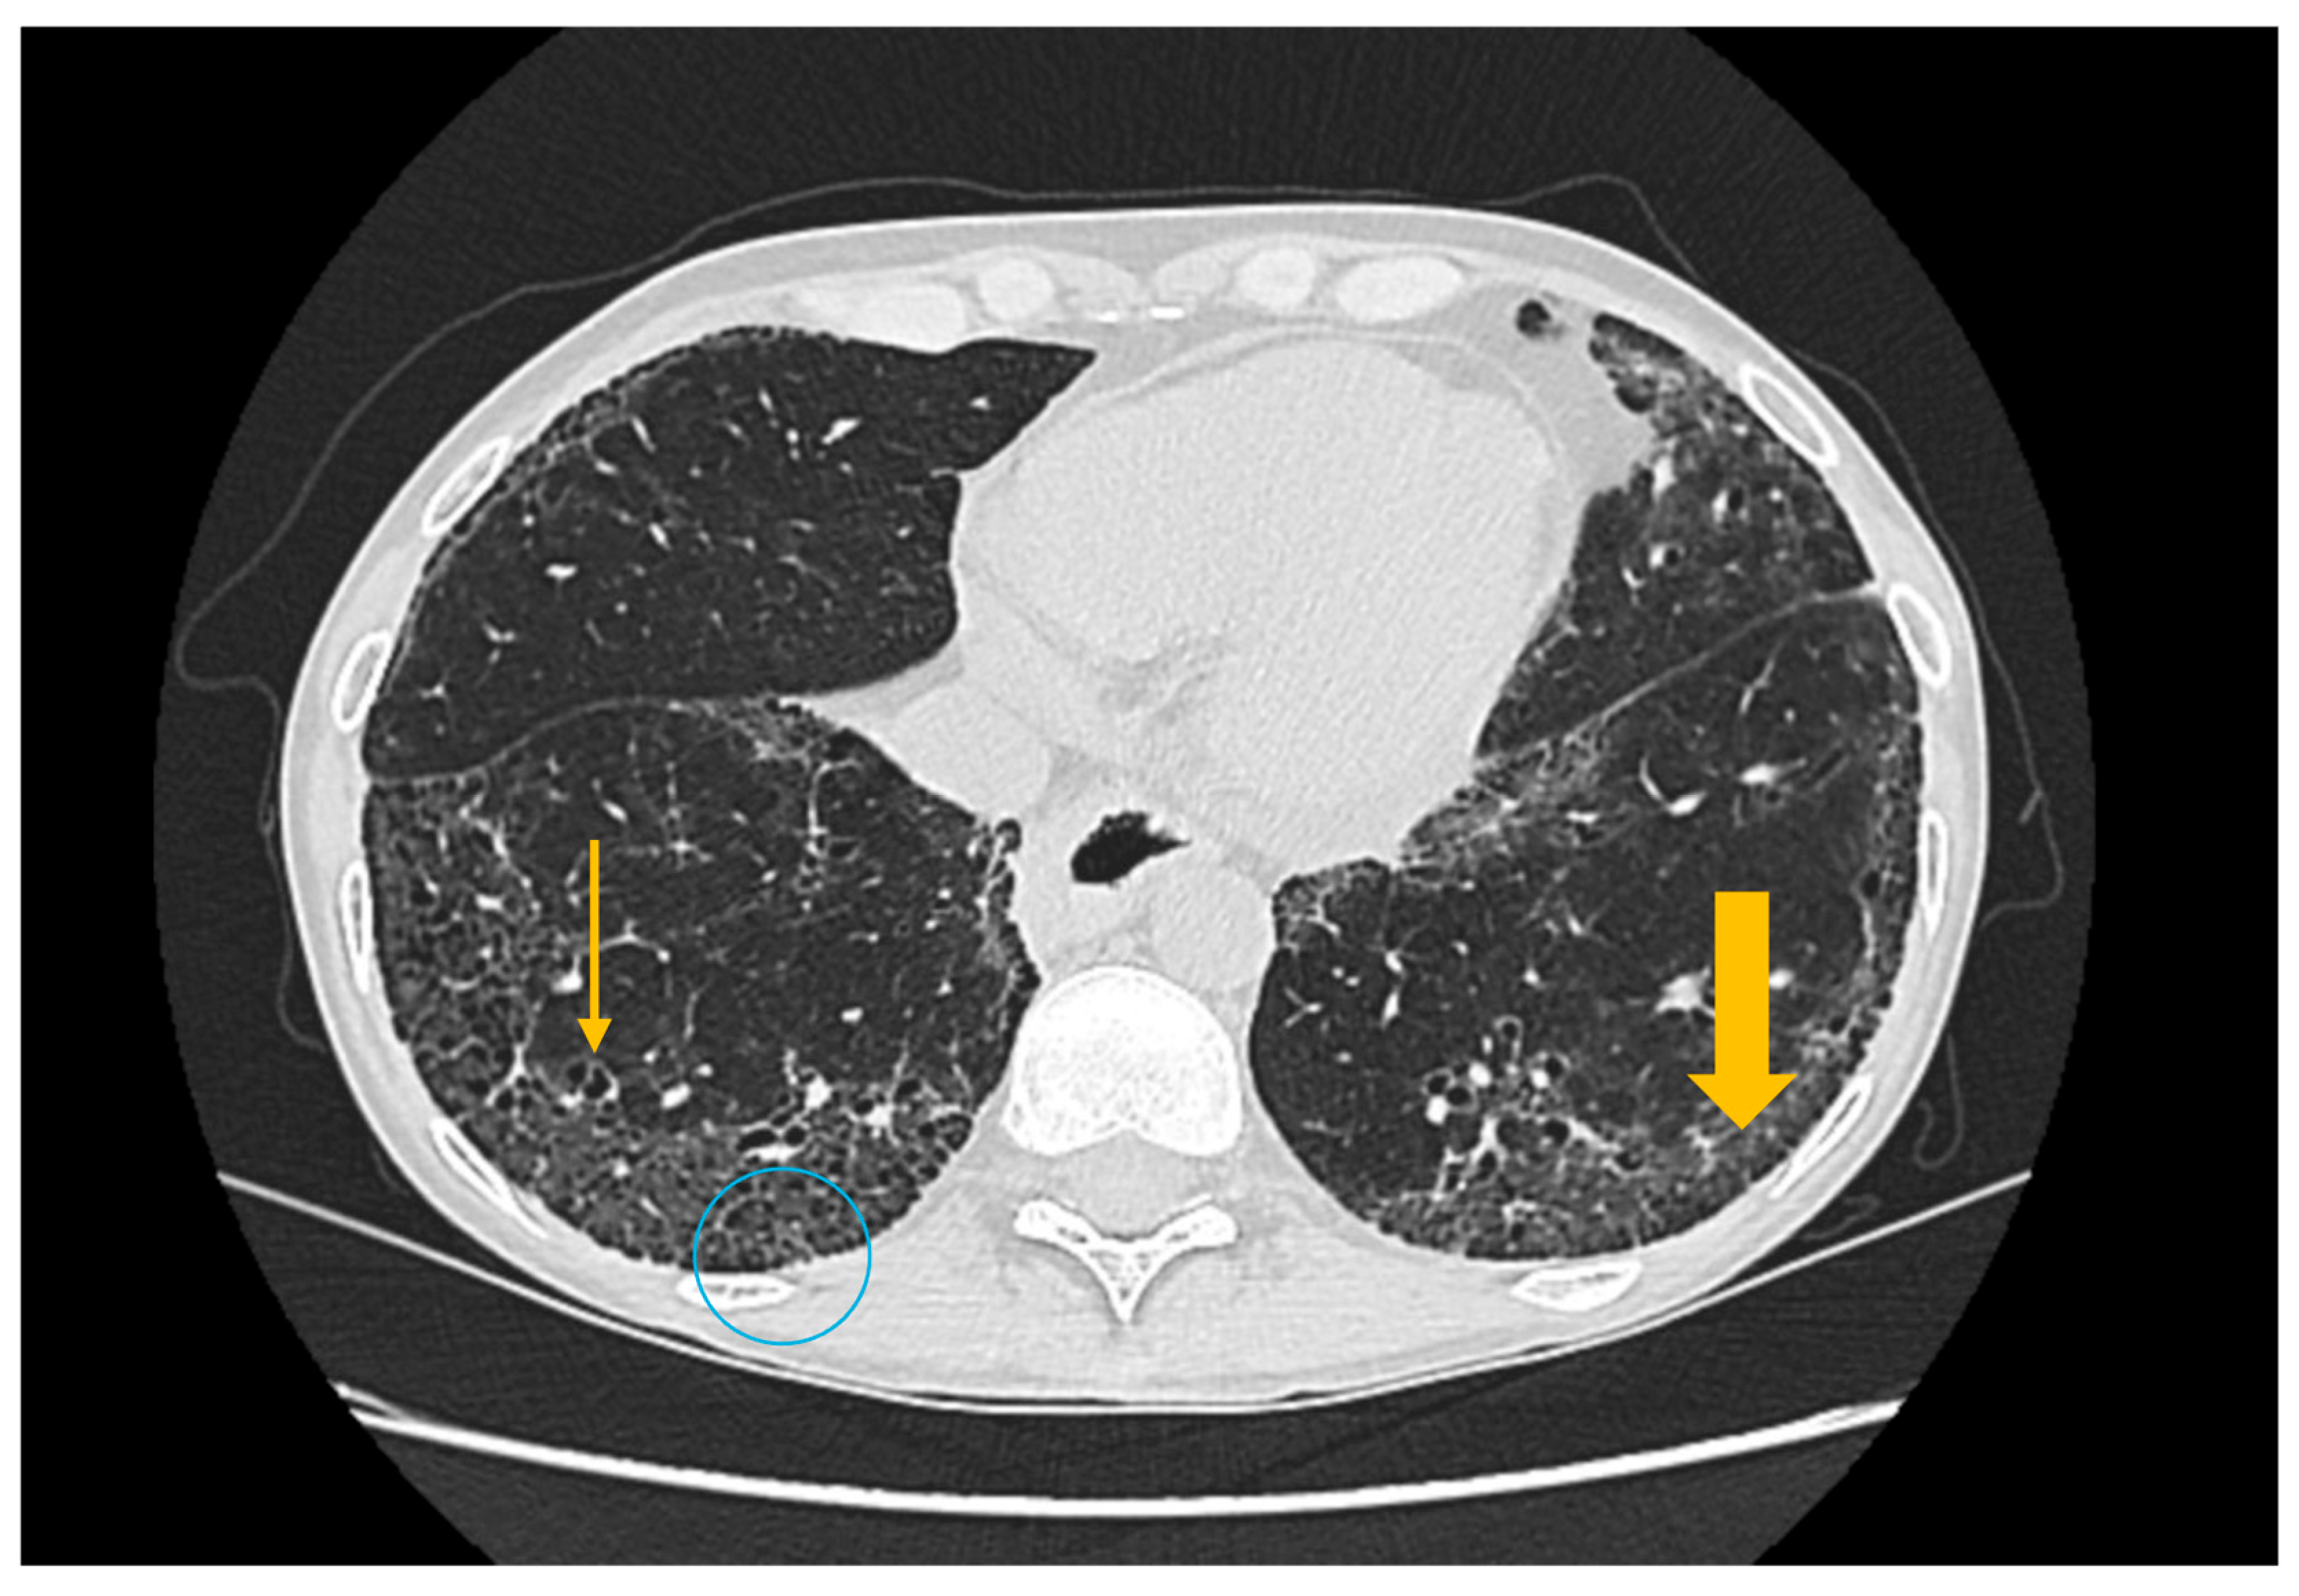

Figure 4. High-resolution computed tomography (HRCT) of the chest in usual interstitial pneumonia (UIP). Axial HRCT image demonstrates subpleural reticulations (thick arrow), traction bronchiectasis (thin arrow), and honeycombing (circle), with an asymmetric distribution and basal predominance, findings characteristic of UIP.

High-resolution computed tomography represents the gold standard for evaluating pulmonary changes in diffuse interstitial lung diseases [48]. This imaging technique has a sensitivity of 100%, specificity of 82%, positive predictive value of 97%, and negative predictive value of 100% for the diagnosis of diffuse interstitial disease [49]. The imaging features vary according to the histologic subtype of involvement (Figure 3, Figure 4 and Figure 5) [50].